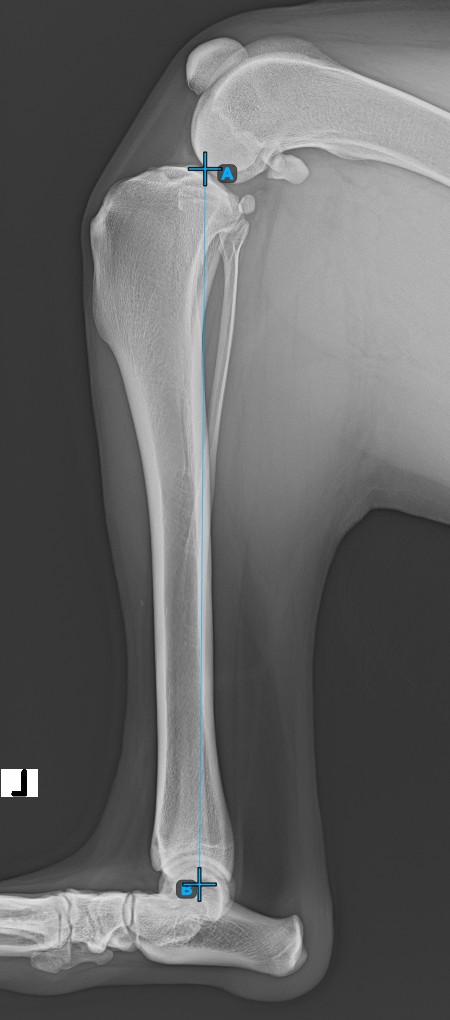

Continue by marking the midpoint of the Cochlea, located at the end of the tibial bone. The line created between the Eminentia Intercondylaris and the midpoint of the Cochlea represents the long axis of the tibia.

The image below depicts the usual placement of the midpoint of the Cochlea.